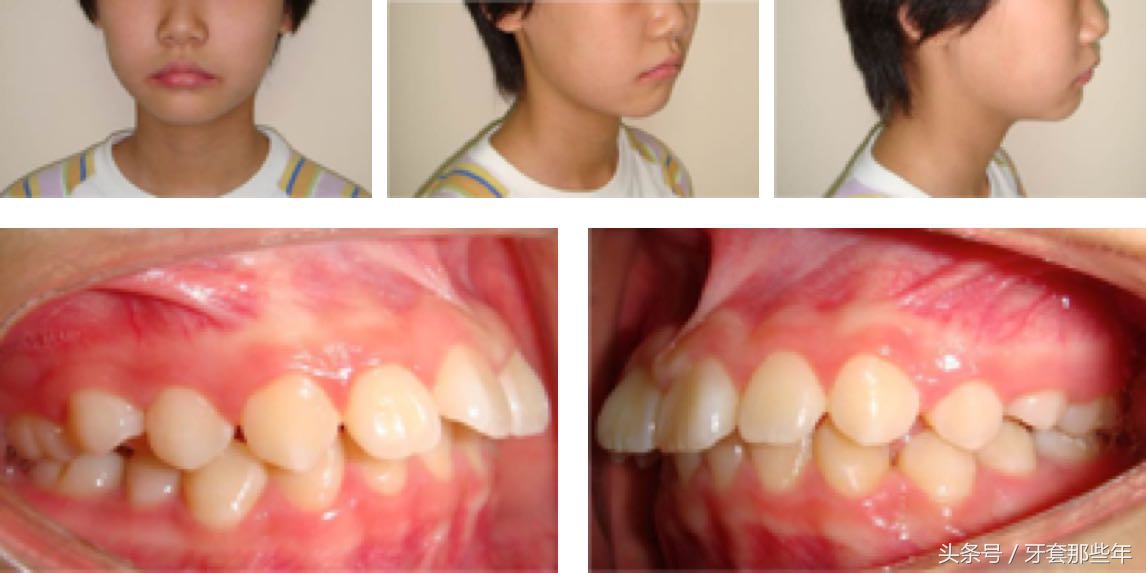

治疗前

这名女孩是典型的龅牙案例,面中部丰满度不够,鼻唇角过小、颏唇沟过深。